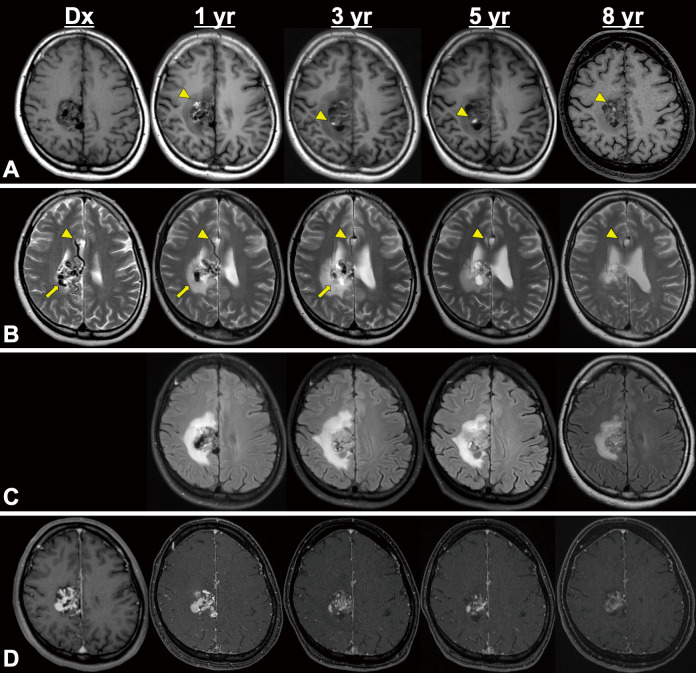

Spontaneous regression of an arteriovenous malformation (AVM) is a rare condition observed in 0.3%-1.3% of patients with AVMs and is most likely caused by hemorrhagic events. The regression of an unruptured AVM is rarer than that of a ruptured AVM. Moreover, due to its low frequency of occurrence, the etiology and natural course of spontaneous regression of an AVM is still unclear. This is the first report presenting a case of a spontaneous regression of an unruptured AVM caused by a gradual drainer vein thrombosis that was suspected to result from hypercoagulability due to protein S deficiency.